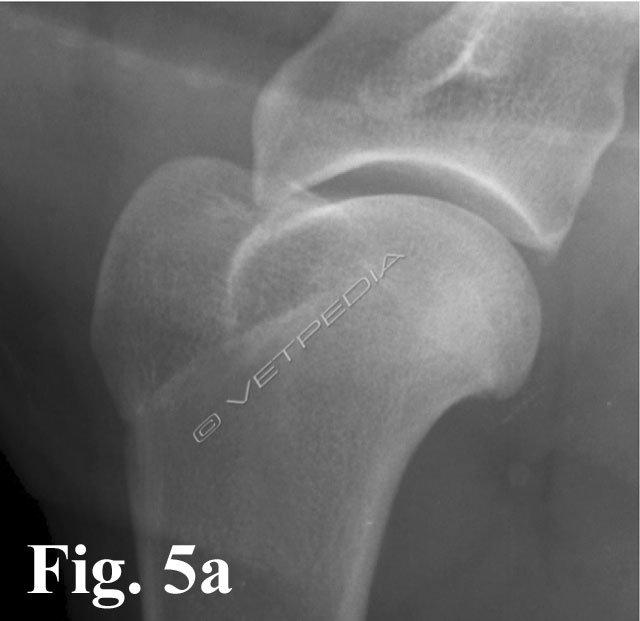

La corretta diagnosi di queste forme iniziali ci consente di indirizzare il paziente verso un approccio chirurgico o conservativo. In caso di diagnosi di OC, è consigliabile monitorare radiograficamente la lesione, con controlli a distanza di circa 2/3 settimane, in modo da valutarne l’evoluzione: guarigione spontanea versus formazione e sollevamento del lembo osteocondrale. Nei casi in cui la lesione è localizzata medialmente, la proiezione medio-laterale neutra potrebbe non consentirci di evidenziare il difetto osteocondrale o di sottostimarne l’estensione (Fig. 5a). E’ consigliabile a tal proposito eseguire una proiezione medio-laterale con rotazione esterna dell’arto, in modo da esporre al fascio radiogeno tangente anche le lesioni localizzate nel comparto mediale (Fig. 5b). Un’altra evenienza è rappresentata dalla migrazione del lembo osteocondrale che, come precedentemente accennato, nei casi più fortunati potrebbe andare incontro a riassorbimento spontaneo oppure comportarsi da “topo” o “tofo” articolare (Fig. 6). La sede dove più frequentemente tende a localizzarsi è rappresentata dal recesso caudale dell’articolazione (vedi Fig. 2), in casi meno fortunati potrebbe migrare nel comparto craniale, più precisamente nella doccia bicipitale, e determinare un’irritazione meccanica al tendine del muscolo bicipite brachiale. In quest’ultimo caso i sintomi dipenderanno dallo sviluppo di una tenosinovite bicipitale.